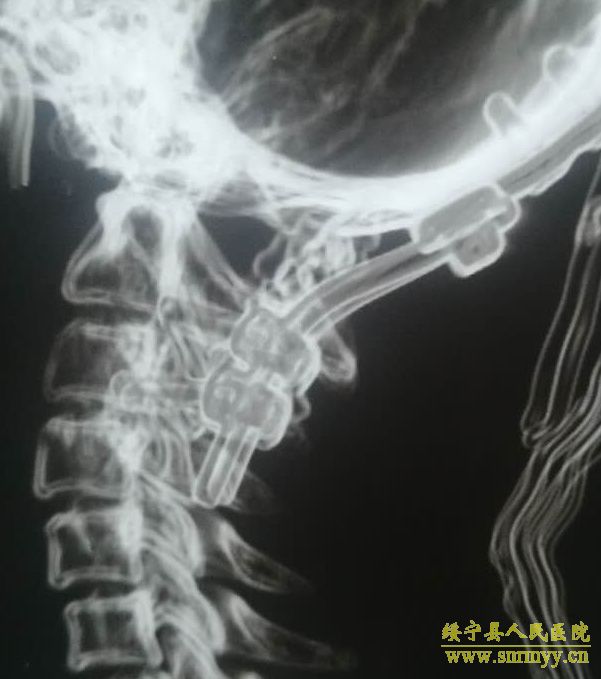

9月2日,我院神经外科在解放军昆明总医院封亚平教授的指导下,成功实施县内首台上颈椎、颅颈交接区手术,这标志着我院神经外科诊疗技术又迈上了一个新台阶。 40岁女性患者,因“头疼头晕伴左侧肢体麻木3年余,加重1月”入院,诊断为环枕畸形合并小脑扁桃体下疝。MRI及CT显示:枕颈融合,寰枢关节脱位,颅底陷入,颅颈角明显变小,小脑扁桃体下疝、延颈交界脊髓明显受压(如图下图所示),此病的症结是那块骨头(红色箭头处)压迫了神经! 想要解决问题,自然就得把那块骨头“掰”下来。骨头虽小,真要把它“掰”下来却绝非易事,需要把颈1-2的小关节撑开,但是,患者的小关节后面还有很粗大的动脉血管(蓝色箭头)挡着,手术难度相当大! 经解放军昆明总医院封亚平教授会诊,我院神经外科为该患者实施了后入路枕骨大孔区减压、寰枢椎脱位复位、枕颈固定、植骨融合术,手术用时短短1.5小时,出血量仅50ml。病人术后神经压迫症状明显改善,第一天开始进食,第二天即可下床活动。 (斜坡颈椎角增大到正常) (术后复查CT及MRI显示寰枢关节脱位复位理想,颅颈角增大基本正常,脊髓受压解除。) (术中无血管、神经损伤) 寰枕畸形是枕骨大孔区、寰枢椎骨质发育异常伴神经系统、椎动脉及附近软组织发育异常的一种先天性畸形疾病。寰枕畸形主要包:扁平颅底、颅底凹陷、寰枕融合、颈椎分节不全、寰枢椎脱位、小脑扁桃体下疝畸形。寰枕畸形可继发于畸形性骨炎、软骨病、佝偻病等。寰枕畸形患者早期临床表现为颈短、头颈痛、活动受限等。对于颈部粗而短的人群而言,寰枕畸形的发病可能相较一般人更高。原因在于,颈部粗短的人在转头活动的过程中,关节的活动度比较大,磨损的程度也更高,因而更容易发病。寰枕畸形合并小脑扁桃体下疝及脊髓空洞症为先天性发育不良所致,成年起病,无任何药物可治疗,手术是唯一有效的治疗办法。起初,患者会逐渐出现颈肩部疼痛,手臂麻木、无力,行走不稳等症。若不及时治疗,晚期预后会很差。(图为 邓泽亮 编辑 雅玲) 神经外科电话0739-2570859 科主任邓泽亮13975968148 副主任黄敏15211991811 |